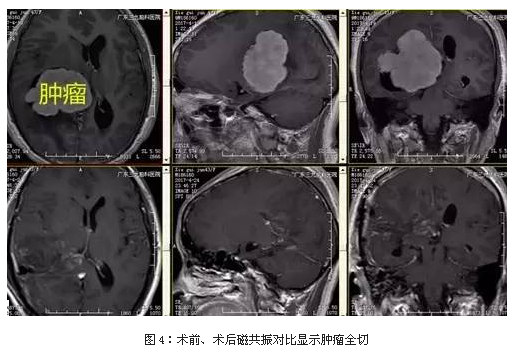

入院后完善术前相关检查,磁共振提示肿瘤强化明显,大小约67.6mm×45.1mm×58.1mm,术前CTA检查示肿瘤血供行全麻下右侧脑室内占位病变切除术,手术由神经外一科主任张良主刀完成,术中肿瘤全切,术后恢复良好。

显微手术是治疗侧脑室脑膜瘤的主要治疗方法,但是因肿瘤位置深、血运丰富、质地坚韧,无论采用哪一种手术入路均会损伤脑组织,因此手术难度高、风险大。术前详细分析患者的临床资料,个体化选择手术入路,运用显微神经外科技术细致操作,可将肿瘤全切,使患者获得较为满意的恢复。本例采用顶枕部入路,采取此人路方式的优点是对脑组织的损伤程度较轻微,可优先处理脉络丛后动脉, 不会损害视放射。 适合应用于体积较大的肿瘤组织切除。本例术后病变完整切除,临床效果良好,未见明确并发症。